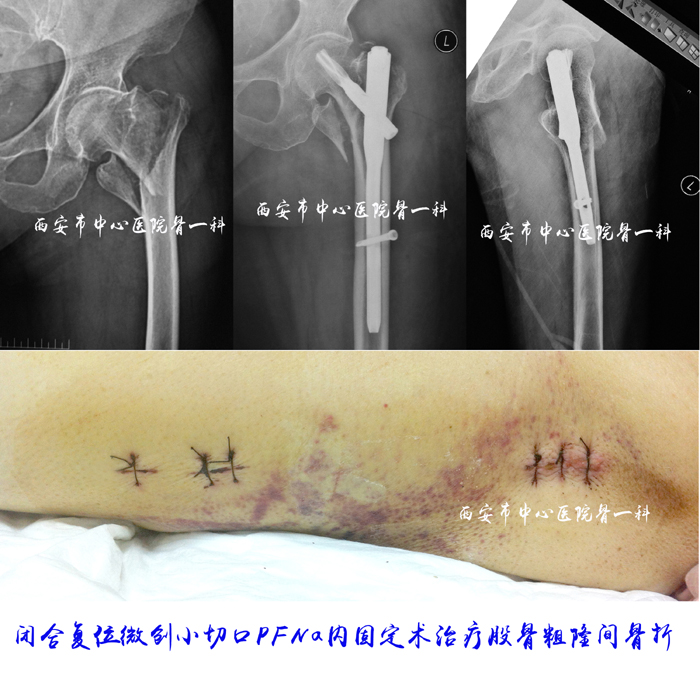

微创病例图片

闭合复位微创小切口PFNa内固定治疗股骨粗隆间骨折1

闭合复位微创小切口PFNa内固定治疗股骨粗隆间骨折2

闭合复位微创小切口PFNa内固定治疗股骨粗隆间骨折3

闭合复位微创小切口PFNa内固定治疗股骨粗隆间骨折4